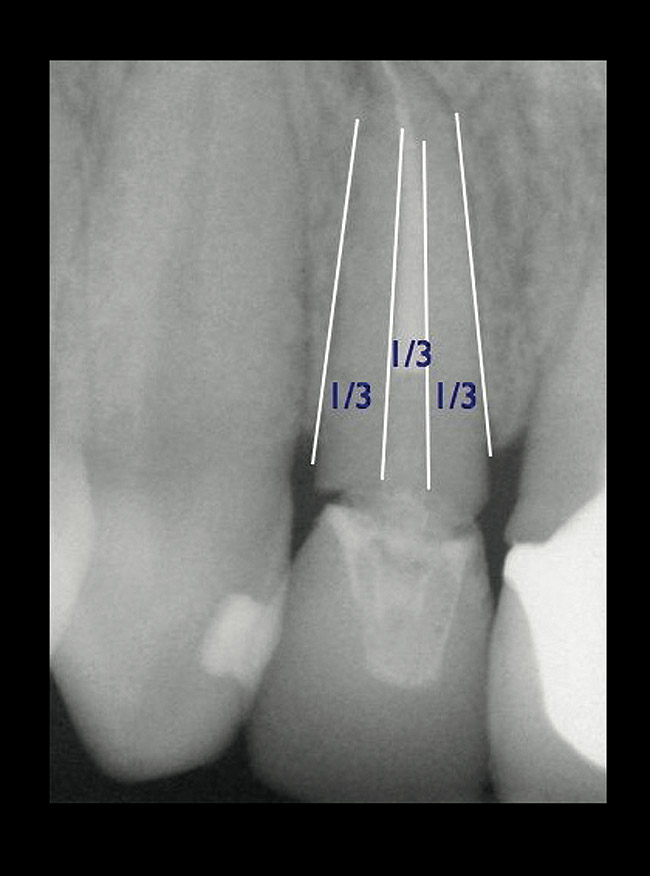

If the tooth has been endodontically treated, the remaining tooth structure relative to the post space needs to be evaluated. The Rule of Thirds is used in this situation. It states that the canal or canal space preparation should not be any wider than one third the mesiodistal root diameter after the endodontic access (Figure 3).3 Once the clinician determines whether adequate tooth structure is present, the second area to evaluate is the distance of the fracture/caries from the crest of bone. To avoid biological width impingement, the minimum distance needed from the osseous crest to the final margin placement is 2.5 mm (Figure 4). As determined in cadaver studies, this consists of approximately 1 mm of connective tissue attachment, 1 mm of junctional epithelium, and 0.5 mm of gingival sulcus.4 This measurement is meant as a guideline and not an absolute number, as it has been shown to have individual variability.5 This actual dimension for the individual patient can be predictably determined by sounding to bone on the adjacent teeth to more closely determine the individual’s biologic width.6